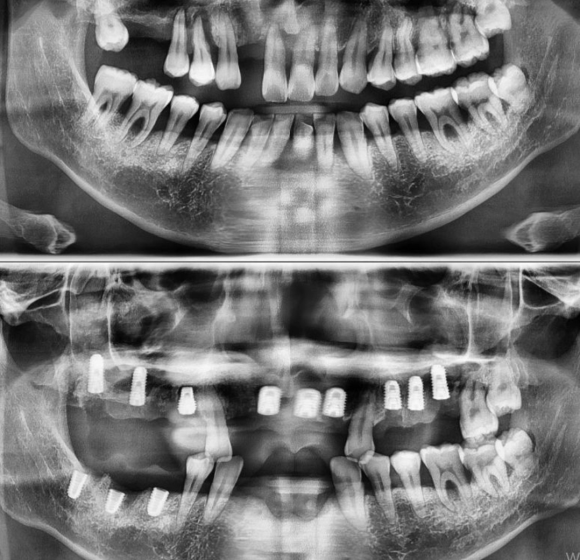

40대 남성으로, 매우 미흡한 잇몸 관리로 인하여 잇몸이 매우 망가져서 치아를 전체적으로 발치하고 임플란트를 계획하게 되었습니다. 남은 뼈가 많이 없기 때문에 할 수 있는 모든 기술 (상악동, 뼈이식, 발치후 즉시식립, 지연식립, 덴샤버, APF 등등...)을 이용하여 차근차근히 식립하고 있습니다....

40대 남성으로,

매우 미흡한 잇몸 관리로 인하여

잇몸이 매우 망가져서 치아를 전체적으로 발치하고 임플란트를 계획하게 되었습니다.

남은 뼈가 많이 없기 때문에

할 수 있는 모든 기술 (상악동, 뼈이식, 발치후 즉시식립, 지연식립, 덴샤버, APF 등등...)을 이용하여

차근차근히 식립하고 있습니다.

술식 접근법 종합 선물 세트 입니다.

상기 환자 틀니를 사용하면 50대가 되었을 때 임플란트 조차 힘들 잇몸을 가지게 되고

평생 음식을 먹지 못하는 상황이 100% 발생하지만

다행히 협조도가 좋아서 올바른 치료를 진행하게 되어 다행입니다.